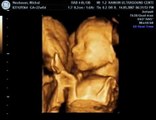

Our baby girl is growing in mother\'s womb and today she let us to see her heart. <br />19 Week Old Fetus Ultrasound with Heartbeat - Gina Family <br />To make compilations we use Videos submitted by the Authors (As claimed). <br />If you the author of the video and you did\'n submitted the video to our channel, please send us private message and we will immediately remove your video..